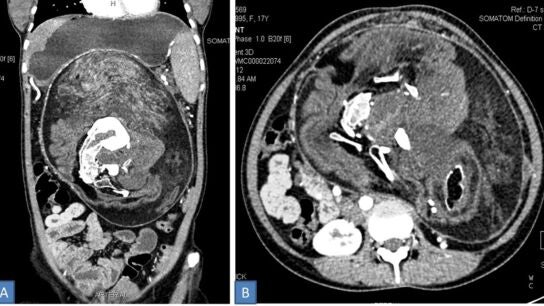

Según recoge 'BMJ Case Reports', la tomografía detectó una masa de unos 25x23x15 centímetros en el interior del cuerpo de la paciente. El tumor, de acuerdo con el artículo del caso, presentaba "áreas de densidad grasa, tejido blando y componentes de densidad calcificada de diferentes tamaños, cuya forma era similar a la de vértebras, costillas y huesos largos".